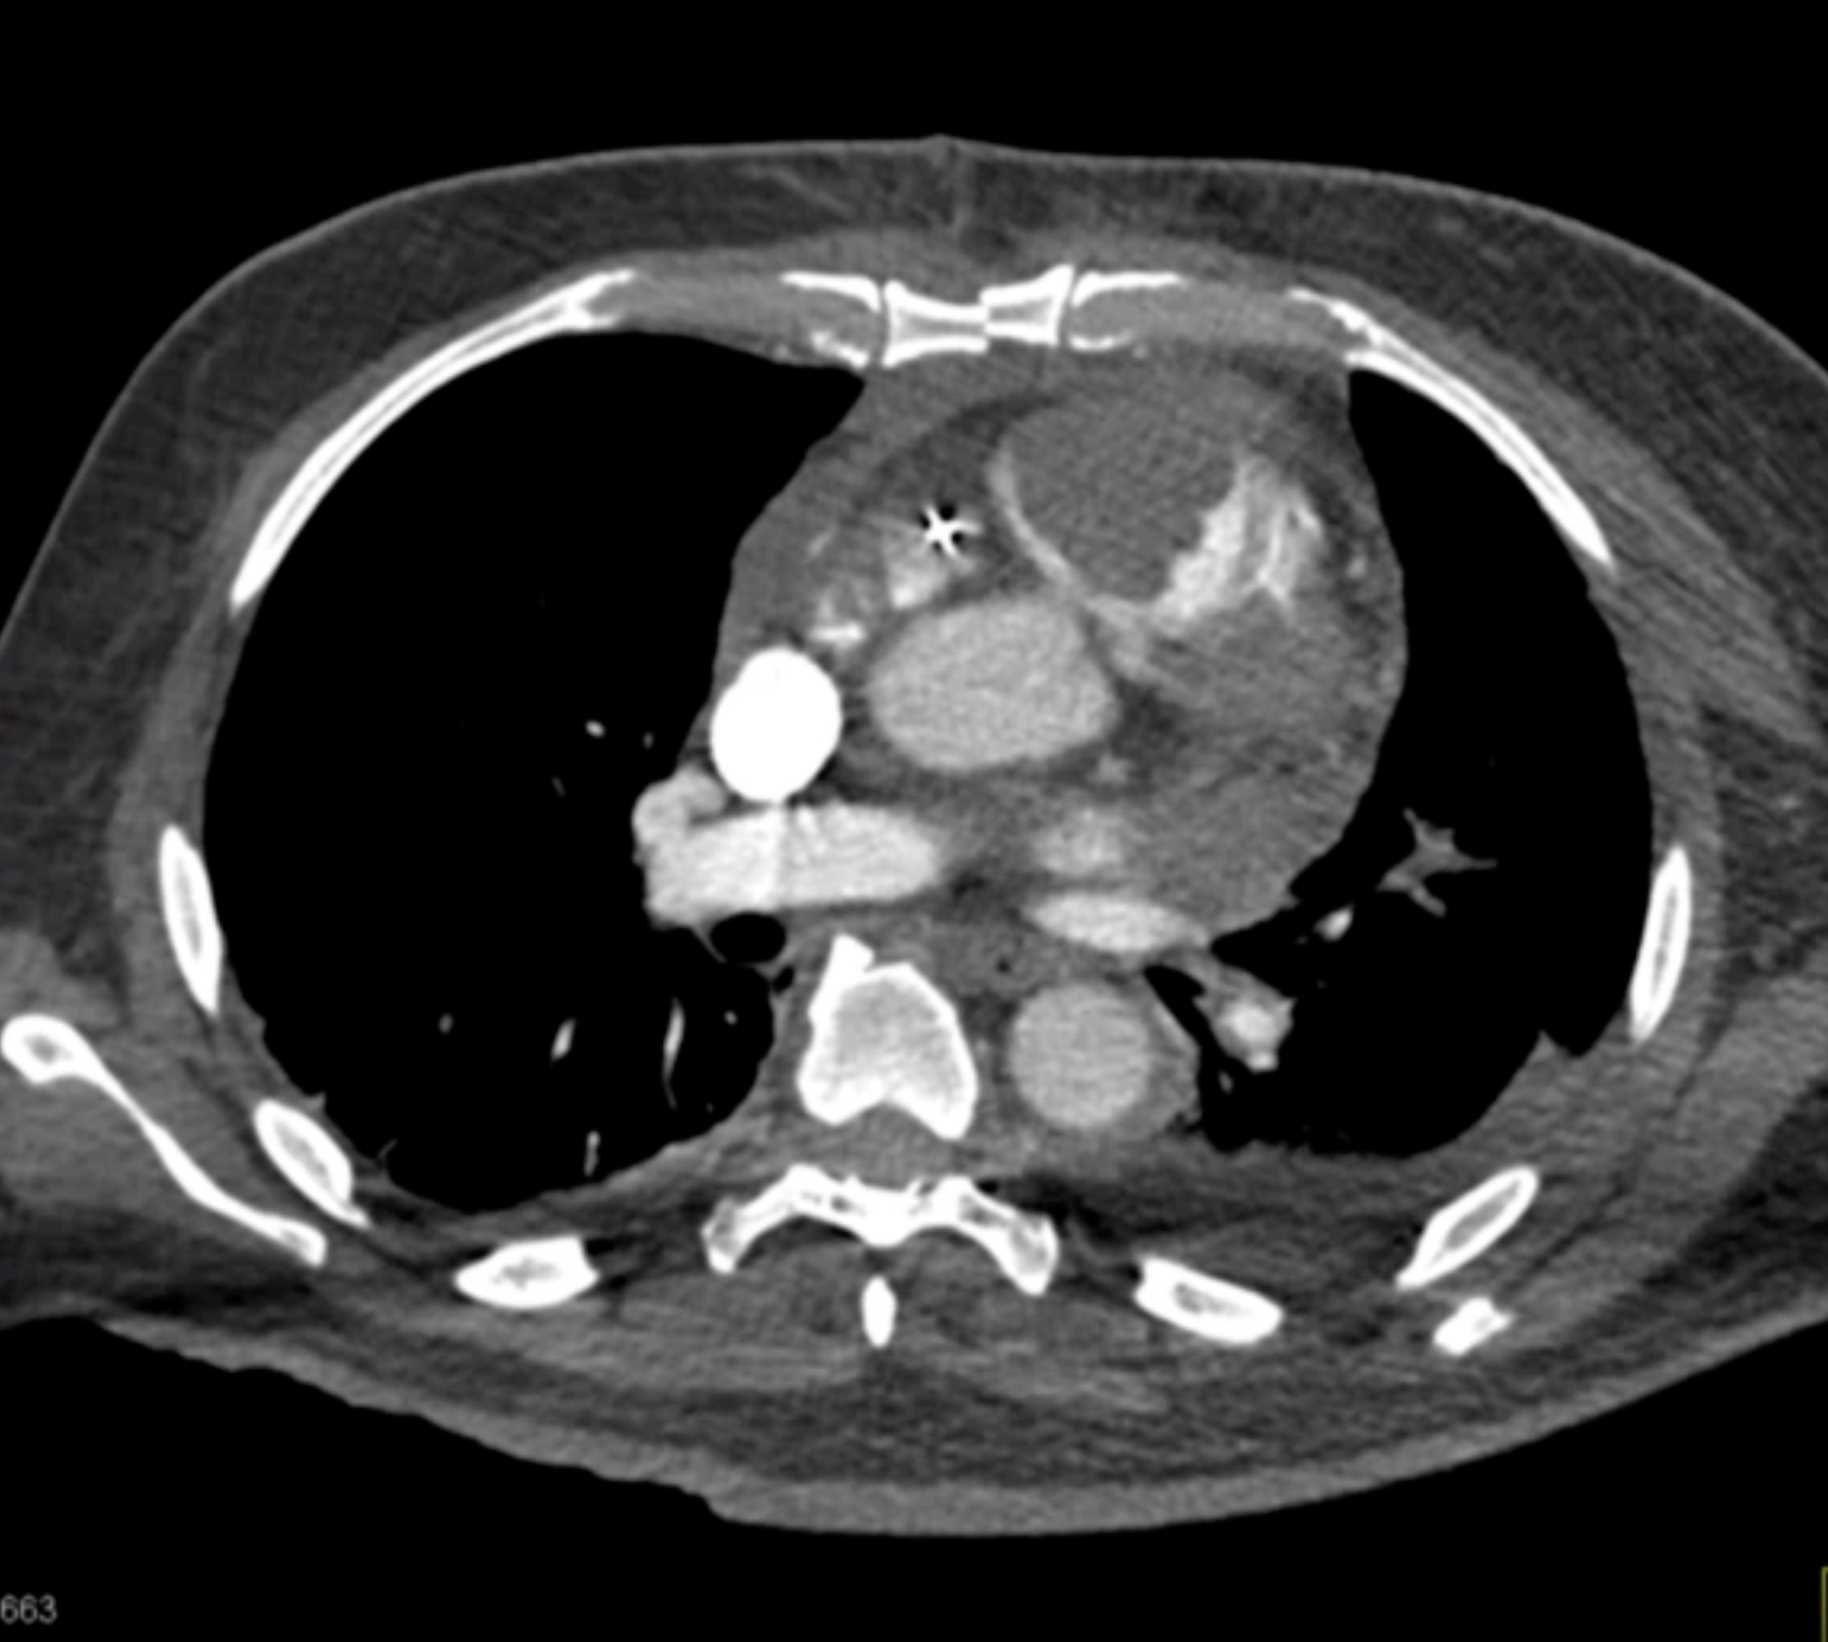

Aortic Valve Repair